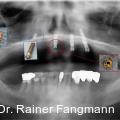

Die Daten der DMS V zeigen, dass in der Patientenaltersgruppe der 65- bis 74-Jährigen im Durchschnitt 12,5 Prozent völlig zahnlos sind. Die zahnlosen Ober- und Unterkiefer stellen eine typische Indikation für herausnehmbaren Zahnersatz dar. Fotos: © Dr. Dr. Rainer Fangmann